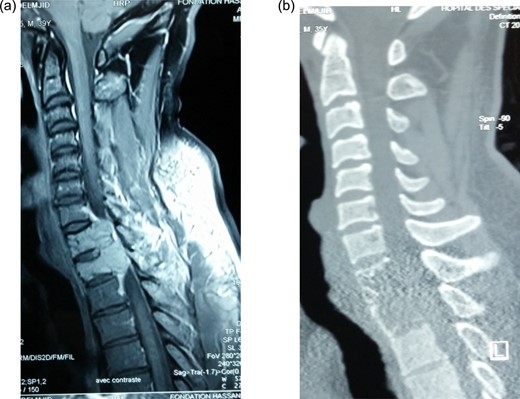

The thoracic spine computed tomography (CT) and magnetic resonance imaging (MRI) showed a tumor involving D1 and D2 vertebral bodies. The lesions are osteolytic eroding the two vertebrae with extension into the spinal canal and enhancing with gadolinium. The patient underwent emergency decompressive laminectomy of D1 and D2 together with stabilization by laminar hooks and rods through C7–D3 (Figs 1 and 2). The biopsy histology revealed to be in favor of a giant cell tumor.

Preoperative gadolinium-enhanced MRI (a) and CT (b) showing expansile lytic tumor at D1 and D2 and compression of the cord at these levels.